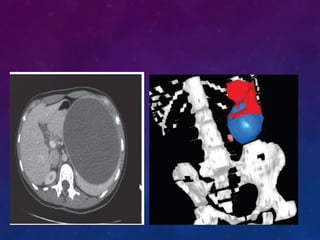

TOMOGRAFÍA COMPUTARIZADA

Con la CT se logra un alto grado de

resolución y detalle del parénquima,

de los vasos y de la relación del bazo

con estructuras vecinas.

La CT actual está más automatizada,

La CT se ha convertido en una

herramienta invaluable en la

valoración y tratamiento del paciente

con traumatismos cerrados,

TOMOGRAFÍA COMPUTARIZADA Con laCT se logra un alto grado de resolución y detalle del parénquima, de los vasos y de la relación del bazo con estructuras vecinas. La CT actual está más automatizada, La CT se ha convertido en una herramienta invaluable en la valoración y tratamiento del paciente con traumatismos cerrados,